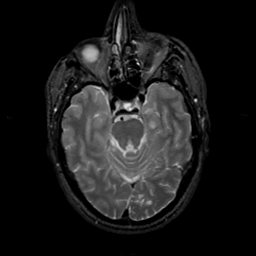

MR Study #22, December 1, 1991 -- Slice #17